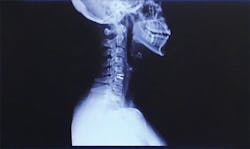

A herniated disk was the cause of years of pain resulting from improper workplace ergonomics

While it did take some time, a neurologist finally confirmed that a herniated disk in my neck was the cause of my pain. I was initially prescribed one month of physical therapy, which eventually turned into three. The co-pays and the unpaid sick time I needed to take away from the office added up to approximately $5,000. Unfortunately, physical therapy was only a short-term fix, and the herniated disk continued to wreak havoc on my life.

Seeing the scar on my neck, resulting from the subsequent cervical disk replacement surgery, patients were more willing to lie back farther and turn toward me when I asked. I frequently ask myself if surgery could have been avoided if I had advocated for myself and required my patients to accommodate me. If I had invested in my loupes and my saddle stool earlier, could that have helped?